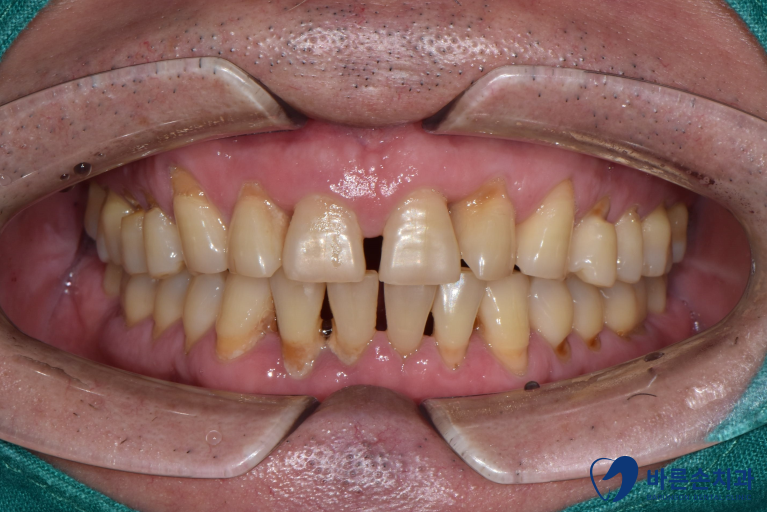

Befoer 23.09.07

<앞니 벌어짐>

치아와 치아 사이가 벌어져있는 상태입니다.

환자분은 위에 앞니 사이가 벌어져 있으시네요.

기능적으로는 큰 문제가 없지만

앞니가 벌어져 심미적으로 개선을 원하셨습니다.